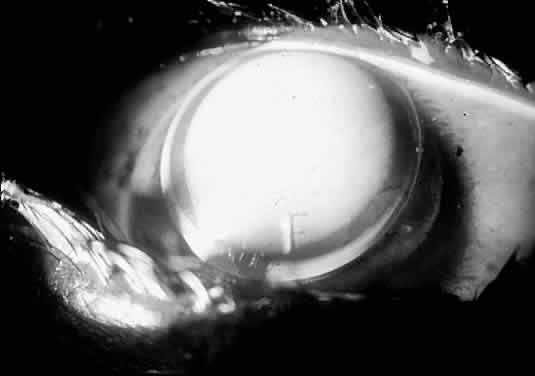

If a diagnostic lens produces an air bubble or extreme fluorescein pooling, then that lens has too large a sagittal depth (too steep), and a lens with a smaller sagittal depth should be tried. A flat lens produces apical touch, requiring that a steeper lens be tried next. The correct lens barely vaults the cone, demonstrating a uniform central fluorescein pattern, as demonstrated in Figures 17 through 19.

Fig. 17. Soper keratoconus lens, the sagittal depth of which is too great. Copious fluorescein is pooling centrally. If this lens were any steeper, it would trap an air bubble centrally

Fig. 18. Soper lens bearing on the cone. This lens's sagittal depth is too small. Occasional air bubbles may be trapped peripherally when a keratoconus lens is too flat.

Fig. 19. Well-fitting Soper keratoconus lens. Fluorescein pattern is uniform over the cone.